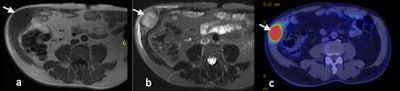

T1-weighted (A) and T2-weighted fat suppressed MRI (B) and PET-CT (C) images of transitional cell carcinoma recurrence within the right anterolateral abdominal wall scar (white arrow).

T1-weighted (A) and T2-weighted fat suppressed MRI (B) and PET-CT (C) images of transitional cell carcinoma recurrence within the right anterolateral abdominal wall scar (white arrow).Transitional cell carcinomas make up the majority of cases. Two cases of seeding from renal cell carcinoma along the cryoablation probe tract have been reported. Intraperitoneal metastases have also been reported following radiofrequency ablation. Port site metastases are associated with poor prognosis. The foci of tumor seeding typically demonstrate similar imaging characteristics to the primary tumor, the Melbourne team concluded.